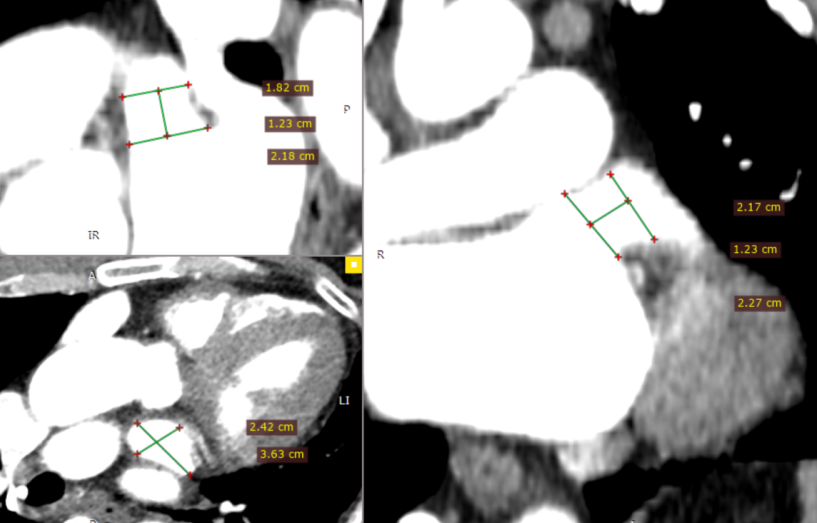

左心房CTA- 多平面测量&3D:锚定区:18.2-21.7mm,开口区:21.8mm*24.2mm。

RAO 30° CAUD 20°测量锚定区:20.3mm;封堵区:24.0mm。

RAO 30° CAUD 20°造影